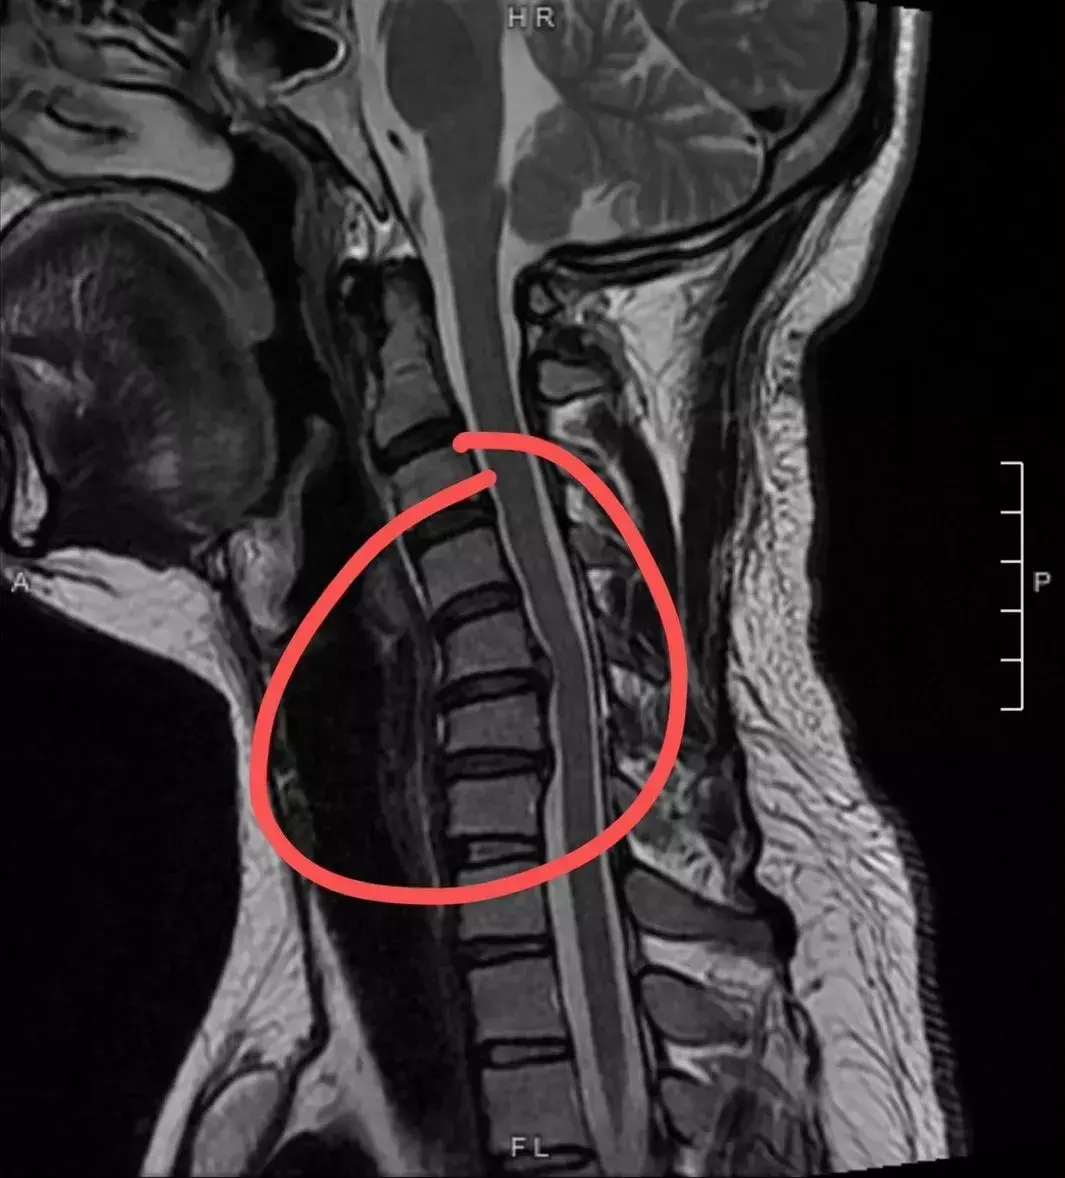

颈椎

颈椎间盘

颈椎病